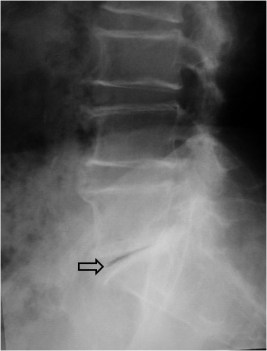

SIGNO DEL SURCO FEMORAL LATERAL

Signo indirecto de rotura del ligamento cruzado anterior (LCA) en la radiografía simple. Se trata de una depresión anormalmente profunda del surco cóndilo-patelar lateral o surco femoral lateral (flecha). Este surco es una pequeña depresión normal en la superficie articular del cóndilo, entre la curvatura que articula con la rótula y la que gira sobre la tibia. El surco anormalmente profundo se produce en la fractura osteocondral impactada, que acontece al tiempo que la rotura del LCA, ya que el mecanismo de ambas lesiones es el mismo: rotación de la articulación y valgo forzado, en el que chocan el platillo tibial contra el cóndilo femoral.

Imágenes de resonancia magnética de la rodilla, que muestran cortes sagitales de una secuencia potenciada en T1. La fotografía de la izquierda muestra como el surco femoral lateral es anormalmente profundo y se acompaña de una disminución de la señal del hueso adyacente por edema medular (flecha blanca). A la derecha, corte en el que debería verse el LCA, ausente por rotura.